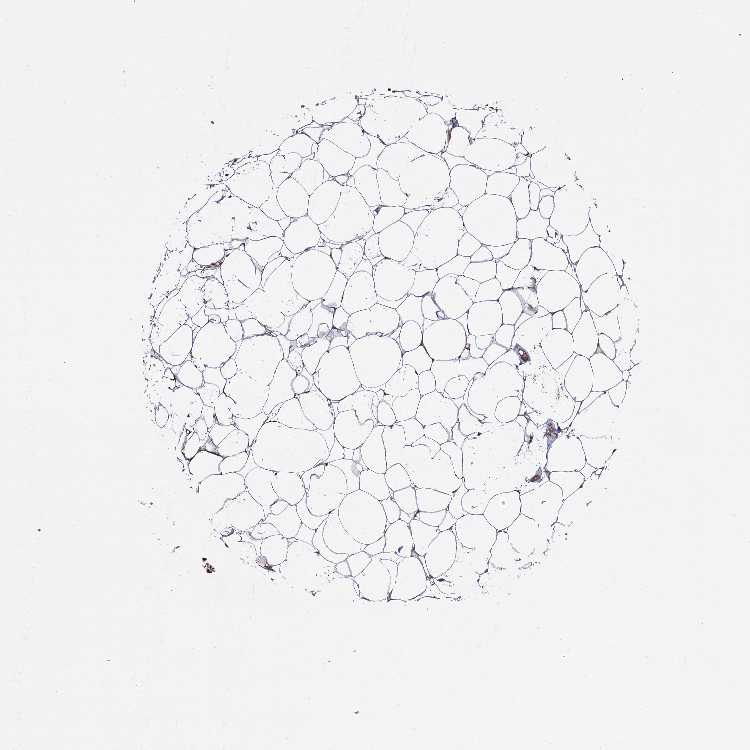

SOFT TISSUE 1 - Antibody stainingi

Antibody staining in the annotated cell types in the current human tissue is reported as not detected, low, medium, or high, based on conventional immunohistochemistry profiling in selected tissues. This score is based on the combination of the staining intensity and fraction of stained cells.

Each image is clickable and will lead to virtual microscopy that enables deeper exploration of all samples and also displays staining intensity scores, fraction scores and subcellular localization as well as patient and tissue information for each sample.

Antibody HPA040845

Fibroblasts Not detected

Peripheral nerve Low